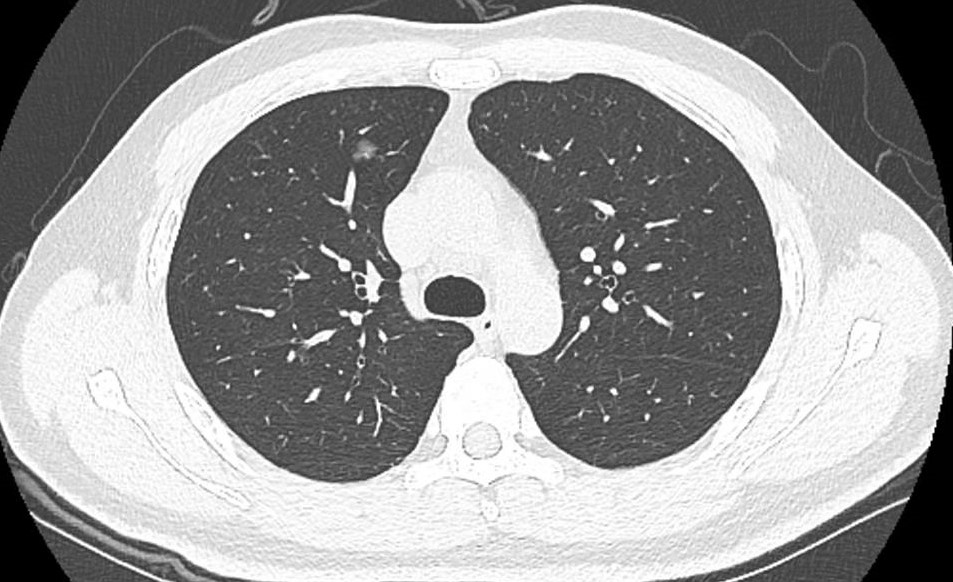

(箭头所指出:术前右肺上叶磨玻璃结节,周围可见分刺征)